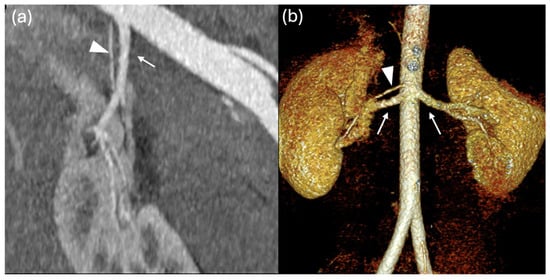

Multiple Renal Arteries as a Potential Contributor to Hypertension in Children and Young Adults

Background: Arterial hypertension in childhood is an increasing health concern, often associated with structural and functional cardiovascular or renal alterations. This study aimed to investigate the prevalence and type of non-stenotic renal artery anatomical variants in children with systemic hypertension and to assess their possible association with cardiac involvement. Methods: A total of 107 children and adolescents with hypertension (mean age 15.4 ± 2.7 years) were evaluated. Hypertension was defined as blood pressure persistently above the 95th percentile for over one year, confirmed by 24 h ambulatory blood pressure monitoring. Patients with known secondary causes were excluded. All underwent renal vascular imaging by CT or MRI and echocardiographic assessment of left ventricular morphology and function. Results: Renal artery anatomical variants were found in 69 of 107 patients (65%), mainly unilateral or bilateral accessory polar arteries. Other anomalies found (left renal vein narrowing or duplication, severe left renal artery stenosis) were excluded from the statistical analysis. Normal renal vasculature was observed in only 32%. Left ventricular hypertrophy was detected in 41%, highlighting a significant prevalence of target-organ involvement. No statistically significant differences were found in terms of hypertension or hypertrophy between patients with renal artery anatomical variants and those without. However, patients with renal anomalies more frequently required dual antihypertensive therapy (p = 0.025). Conclusions: Renal artery anatomical variants, even in the absence of overt stenosis, may contribute to the pathogenesis of pediatric hypertension and complicate its management. Systematic evaluation of renal vasculature should be considered in the diagnostic workup to improve risk stratification and guide management strategies.